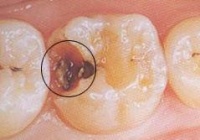

龋齿最容易发生在磨牙双尖牙的咬面小窝、裂沟中,以及相邻牙齿的接触面。前者称为窝沟龋,后者称为邻面龋。儿童发生在牙颈部的龋齿极少,只在严重营养不良或某些全身性疾病使体质极度虚弱时才可见到。根据龋齿破坏的程度,临床可分为浅龋、中龋和深龋。

• 浅龋 龋蚀破坏只在釉质内,初期表现为釉质出现褐色或黑褐色斑点或斑块,表面粗糙。继而形成表面破坏。邻面龋开始发生在接触面下方,窝沟龋则多开始在沟内,早期都不容易看到。只有发生在窝沟口时才可以看到,但儿童牙齿窝沟口处又容易有食物的色素沉着,医师检查不仔细也会误诊或漏诊。浅龋没有自觉症状

• 中龋:龋蚀已达到牙本质,形成牙本质浅层龋洞。病儿对冷水、冷气或甜、酸食物会感到牙齿酸痛,但刺激去掉以后,症状立即消失。这是在为牙本质对刺激感觉过敏的缘故。中龋及时得到治疗效果良好。

• 深龋:龋蚀已达到牙本质深层,接近牙髓,或已影响牙髓。患儿对冷、热、酸、甜都有痛感,特别对热敏感,一败涂地去掉以后,疼痛仍持续一定时间才逐渐消失。这时多数需要作牙髓治疗以保存牙齿。

深龋未经治疗,则牙髓继发感染或牙髓坏死。细菌可以通过牙根达到根尖孔外,引起根尖周围炎症。可能形成病灶感染。牙冠若已大部破坏或只留残根时,应将其拔除。